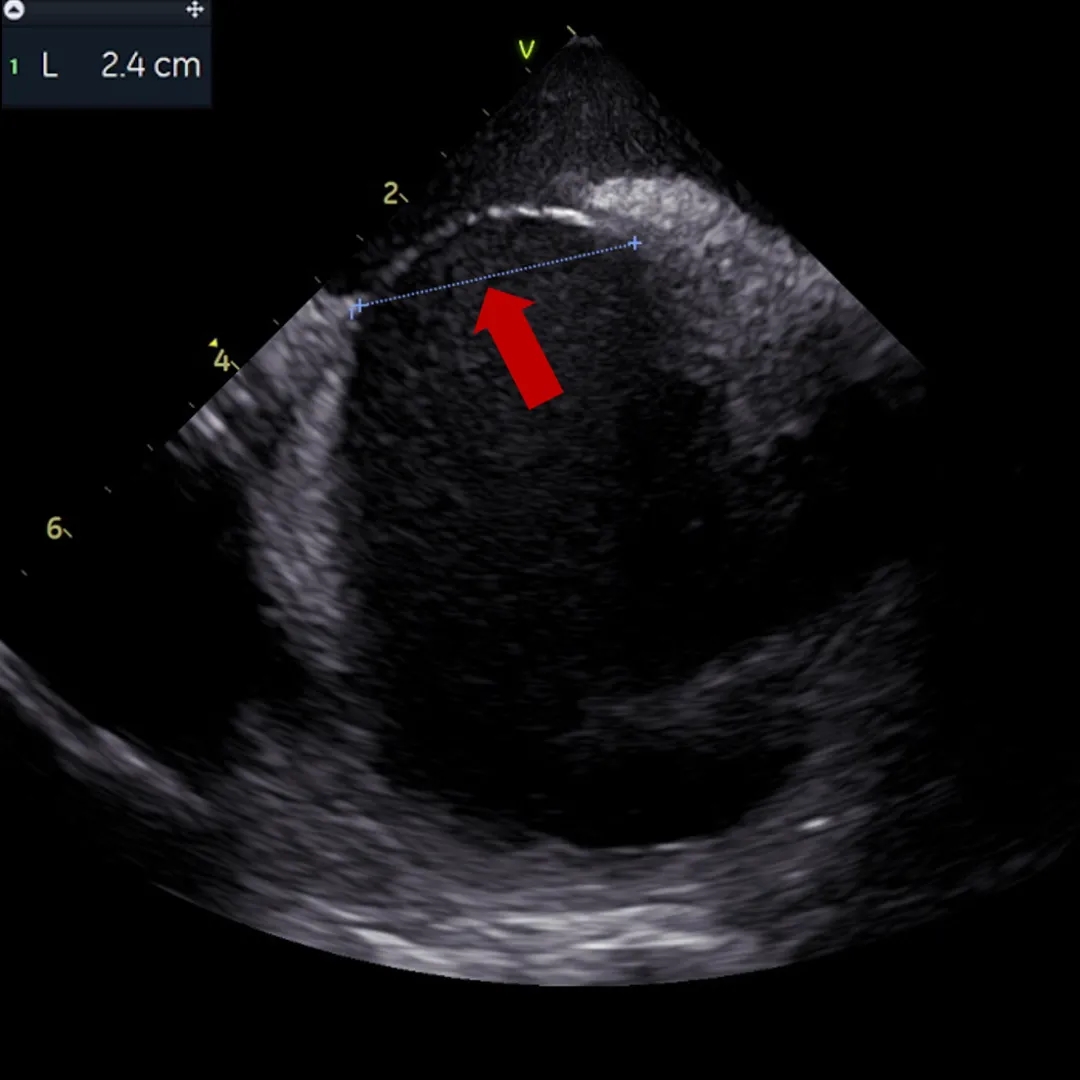

ICE下可见明显长隧道PFO

ICE下测量膨出瘤基底24mm